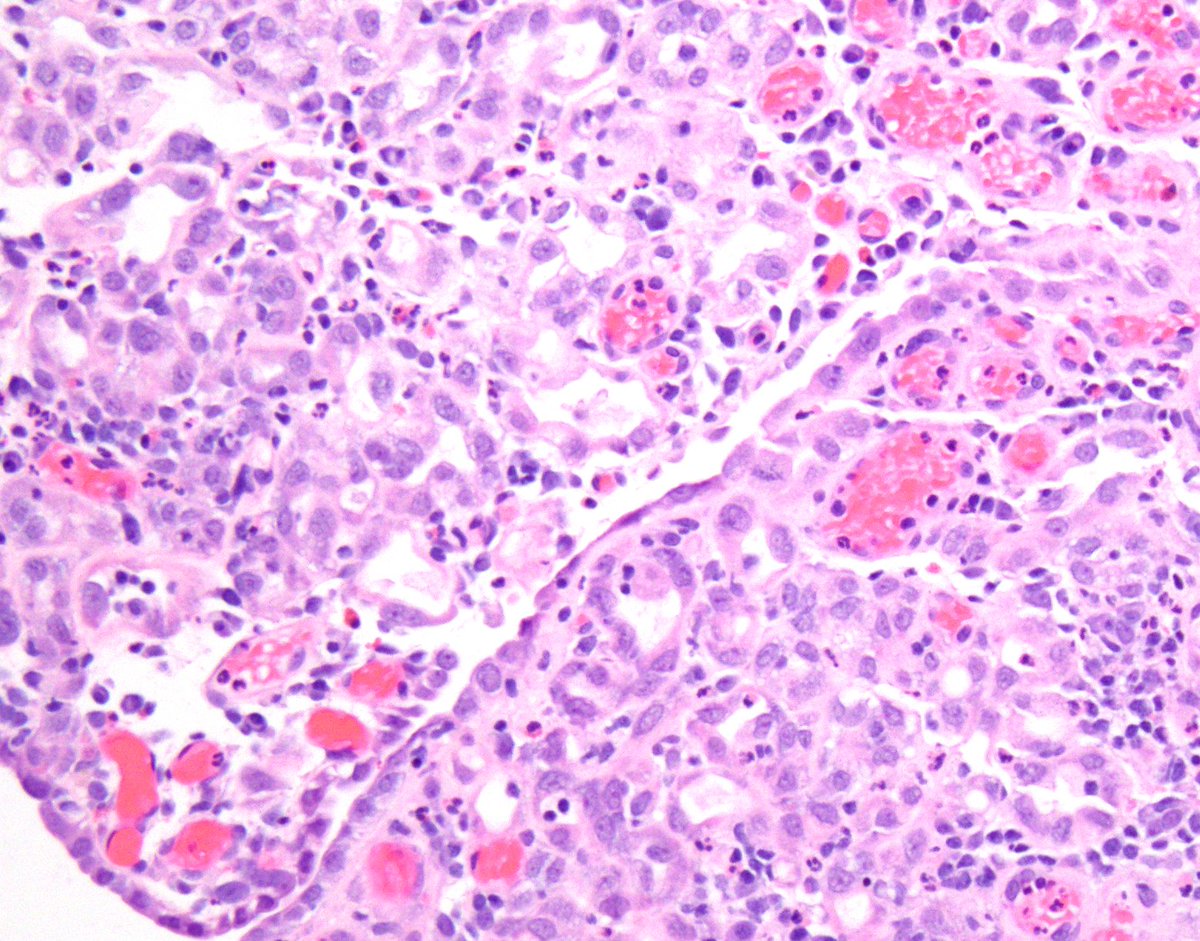

Rare diagnostic pitfall Bladder mass in a 70yo male. Epithelioid cells with focal spindle cell morphology and atypical mitoses, marked variation in nuclear size and shape, hyperchromatic, occasional intranuclear inclusion. Note the absence of in situ carcinoma. see next tweet.

This is a case of metastatic melanoma to bladder. This mass was black in cystoscopy. Less than a 30 are reported in the literature, but the true prevalence is higher, autopsy series on melanoma patients reported 3-18% prevalence. M : F = 15 : 8. #gupath #pathology #bladdercancer